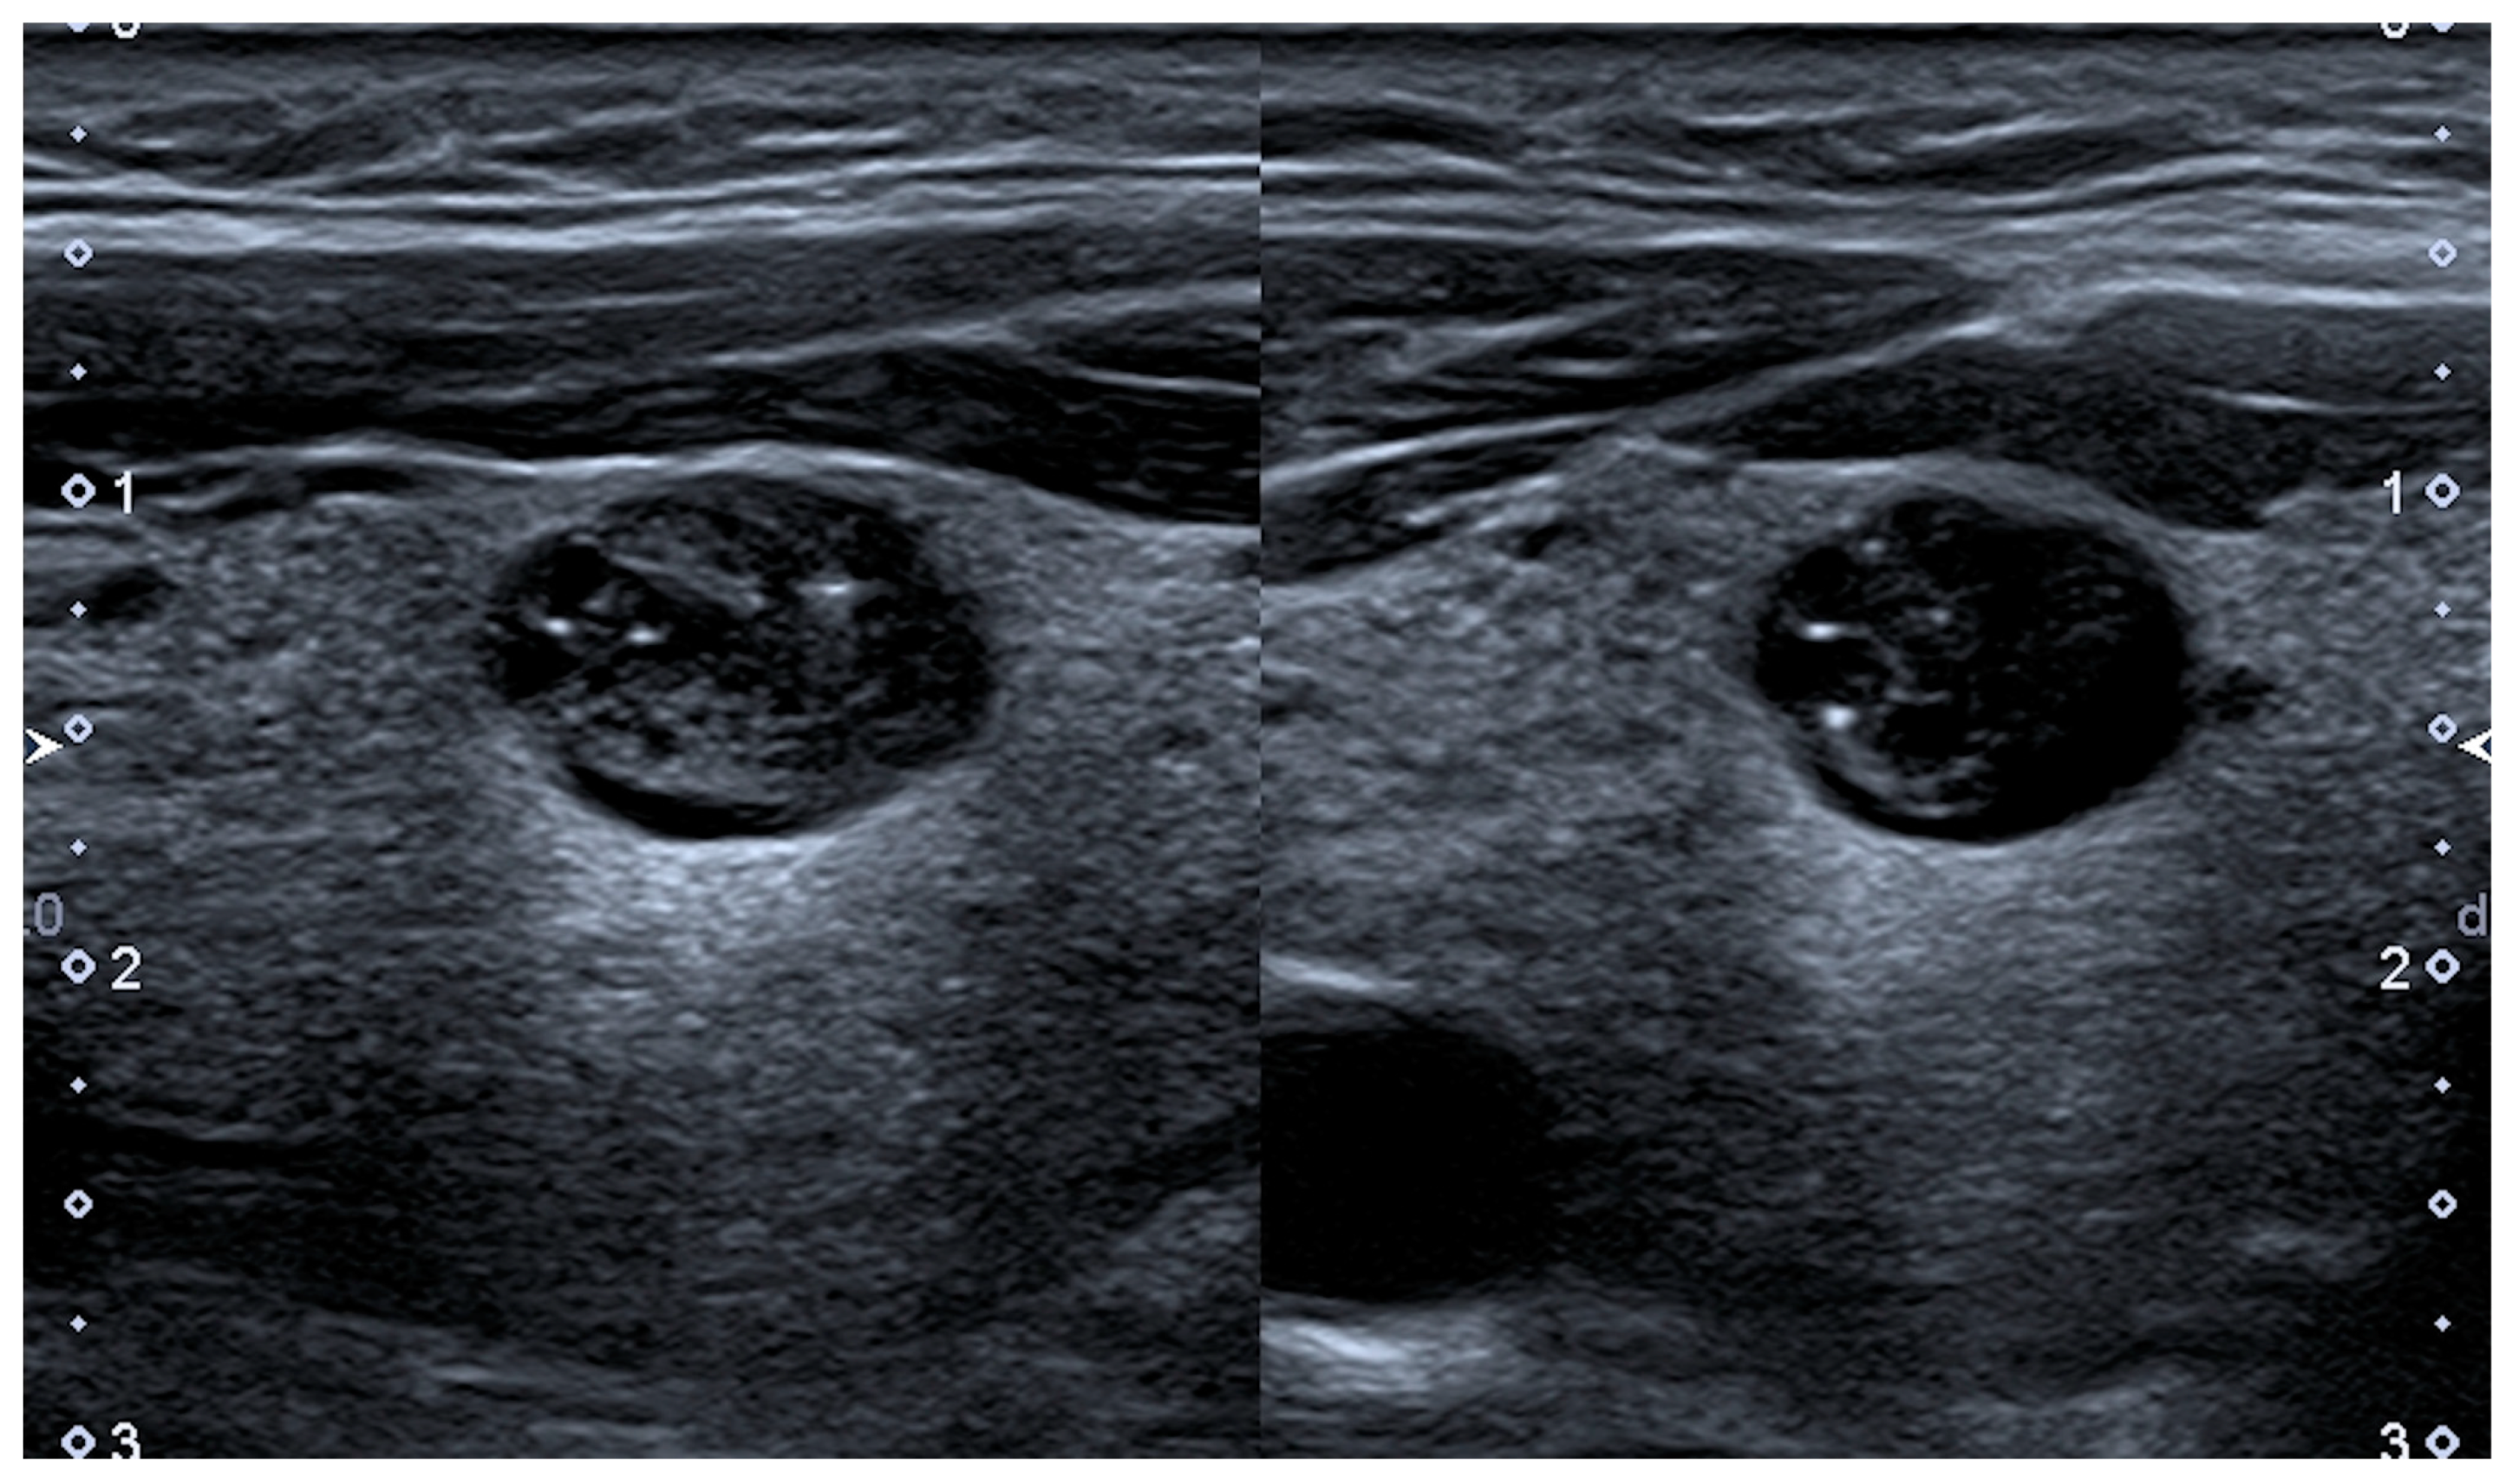

4.1. Shrinking Nodules